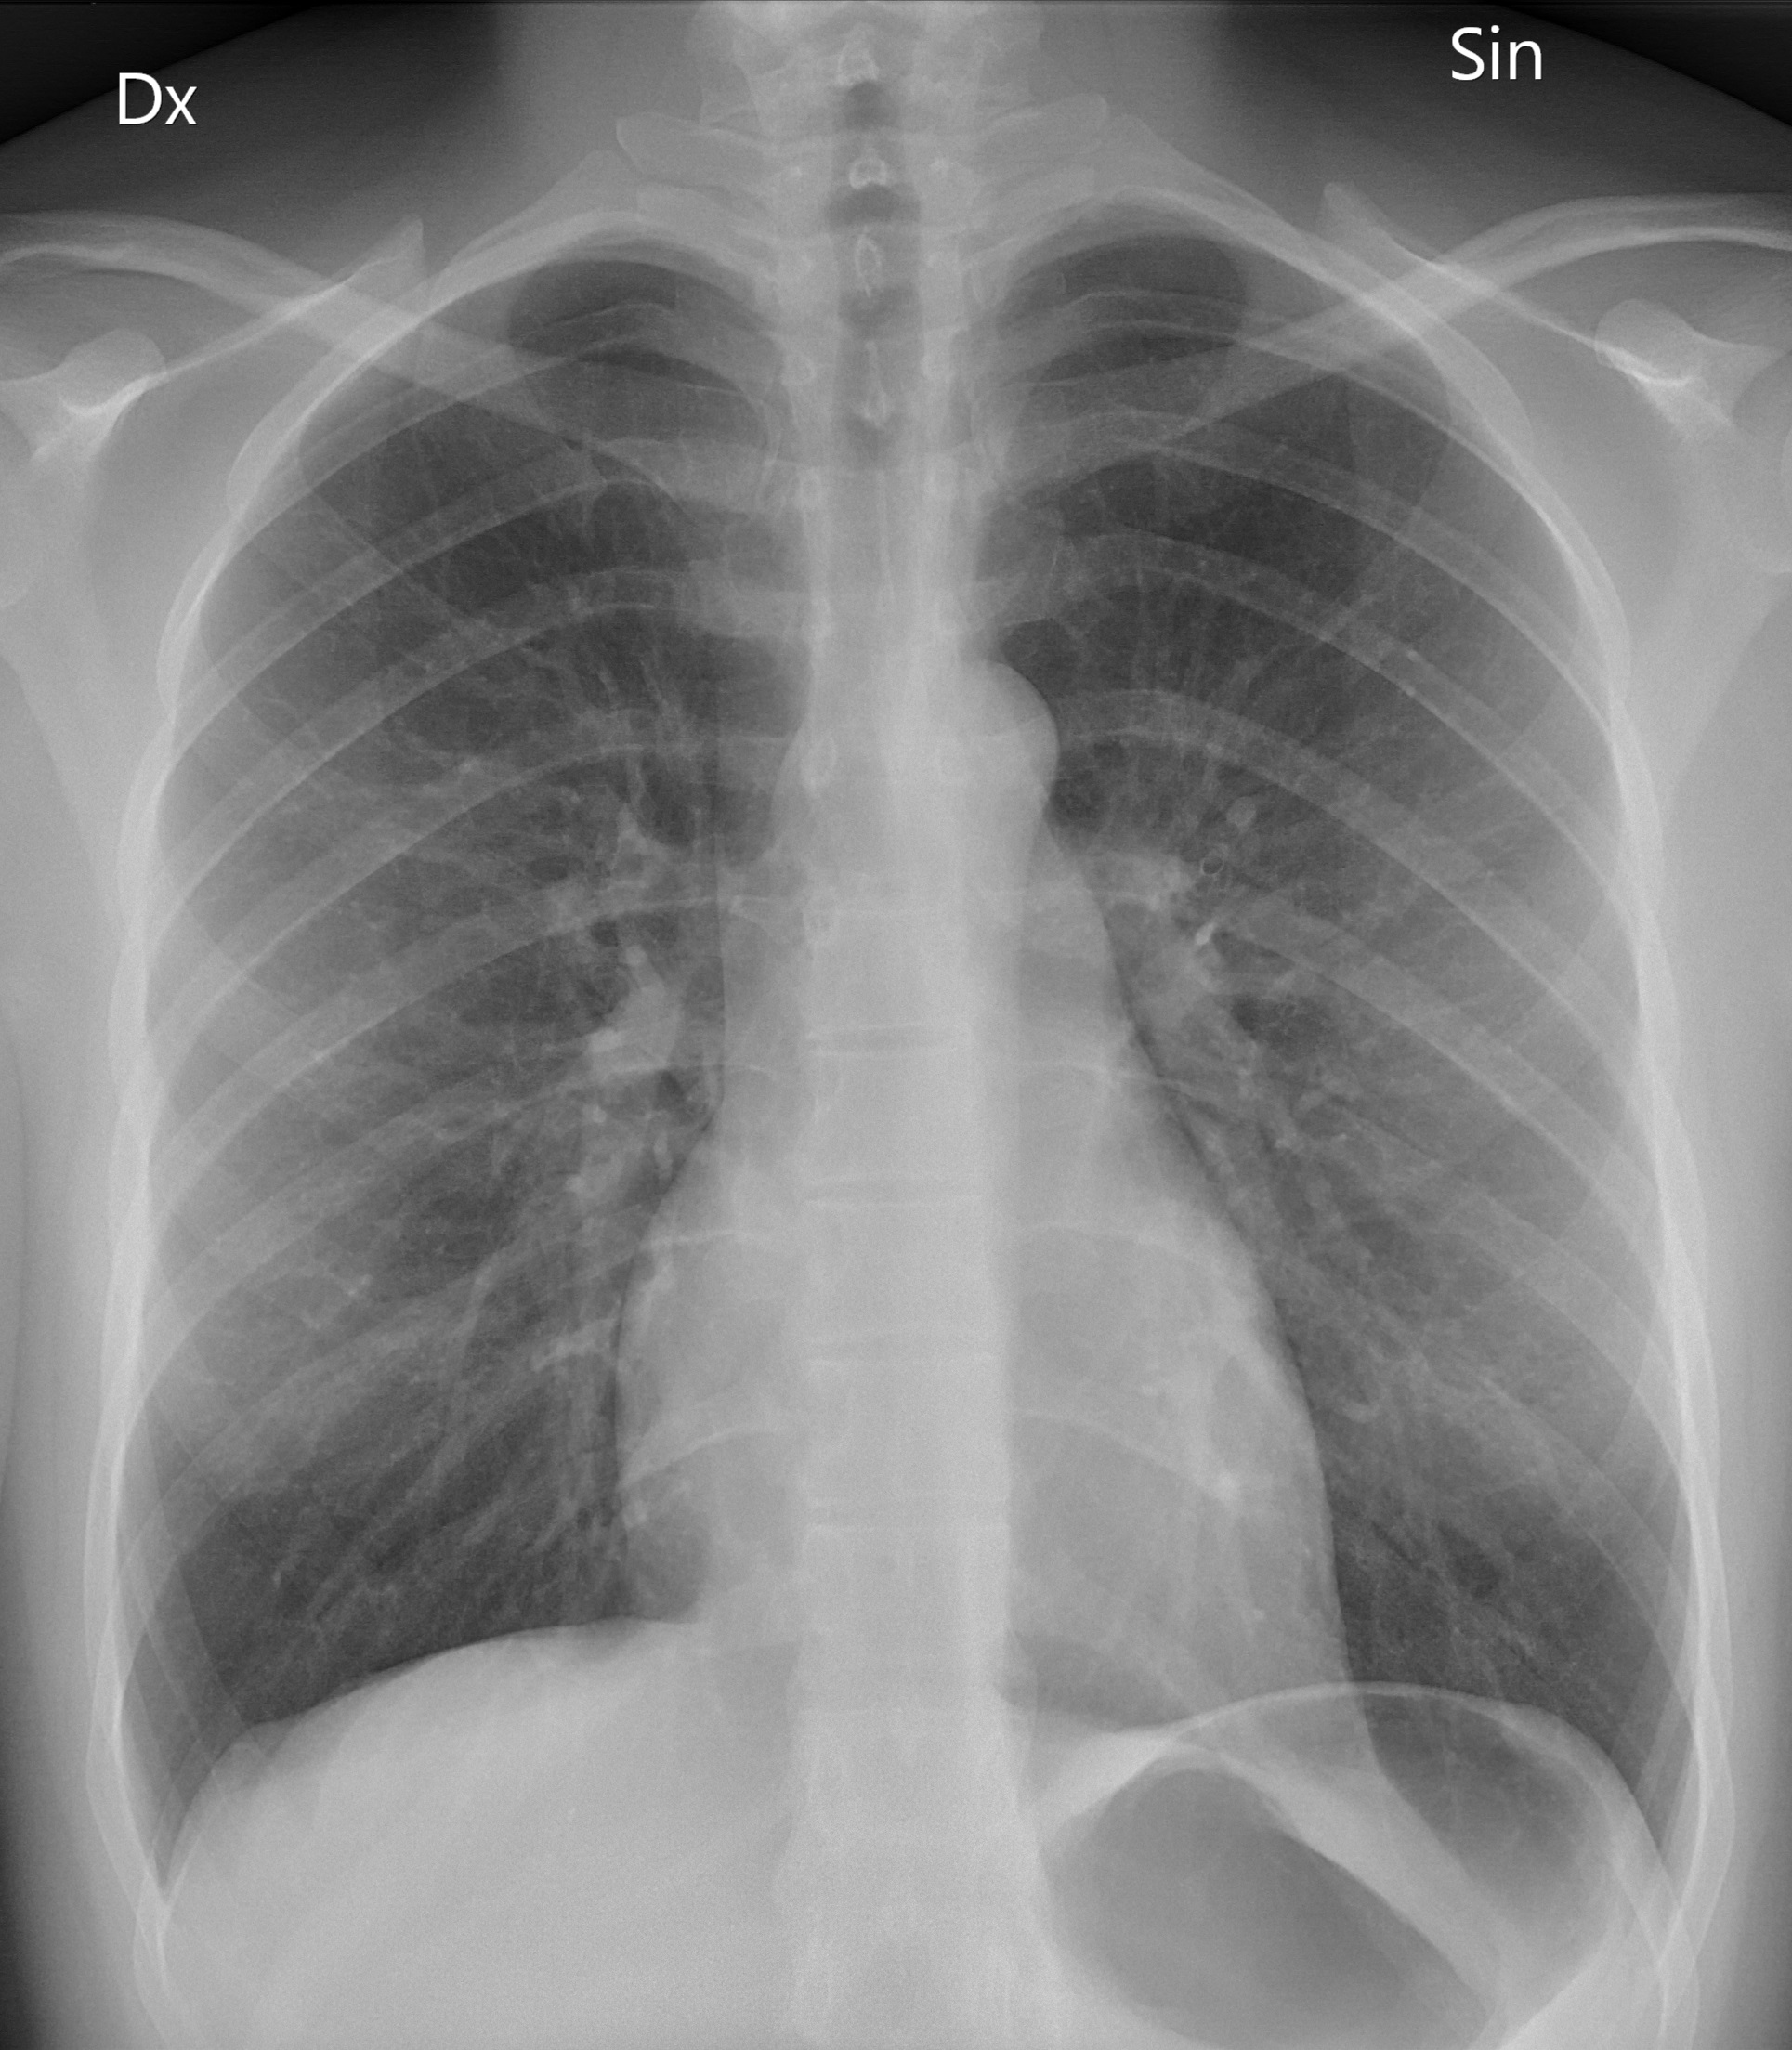

O diafragma é um músculo, que demarca a fronteira entre as cavidades supra e infra. É uma estrutura fina e com uma posição atípica, no sentido em que se estende perpendicular aos pulmões, transversal ao corpo, o que não é visível nos restantes órgãos.

Imagine-se, na imagem da minha visão, a ausência de pulmões – acima – e de intestinos e baço e estômago – abaixo; mas, ainda assim, a posição do diafragma em tudo semelhante com a que manteve, em vida, estendido e cativo nos mesmos domínios.

As costelas, ainda ligadas entre si pelos músculos intercostais, e mantendo também a sua posição natural – apenas ausente o plastrão, o esterno.

Da janela elevada do edifício, entrou um raio luminoso de Março, reluzindo no tórax do animal morto. Os músculos – quer os intercostais, quer o diafragma – translúcidos por natureza, retiveram parte da luz, permitindo passagem à restante e, assim, iluminou-se um oceano vermelho, consumido por rasgos capilares de cor intensa, vívida como nenhuma outra, talvez pelo contraste automático com o envolvente.